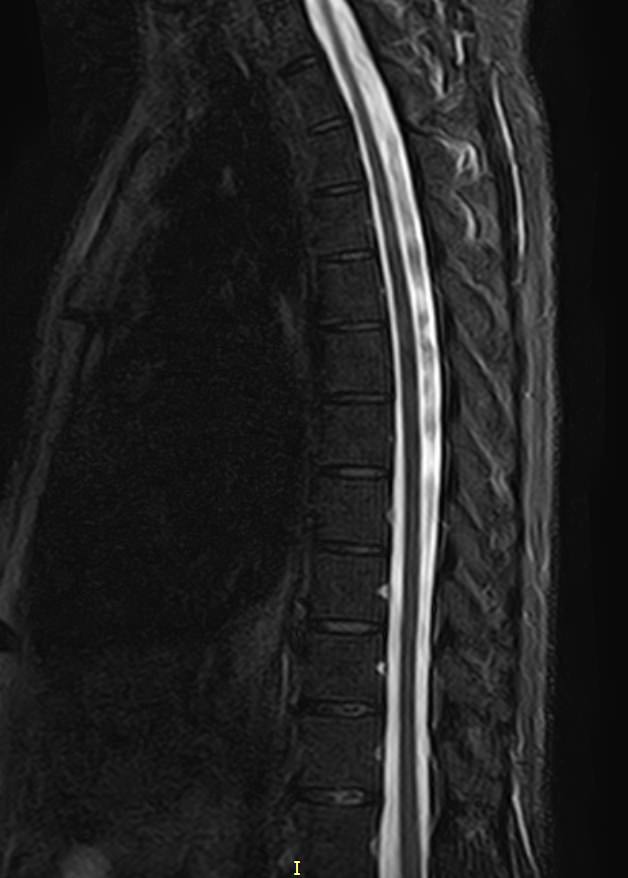

Магнитно-резонансная томография является наиболее чувствительным и эффективным методом диагностики различных заболеваний позвоночника. Метод позволяет оценить состояние костных структур позвонков, позвоночного канала с расположенным в нем спинным мозгом и окружающих мягких тканей, кроме того является основным способом диагностики демиелинизирующих заболеваний спинного мозга.

В клинике «Доступная медицина» установлен новейший высокопольный томограф экспертного класса TOSHIBA VANTAGE TITAN 1,5 Тесла, на котором выполняется комплексное обследование позвоночника. За счет высокой напряженности магнитного поля аппарат при сканировании создает изображения на плоскости превосходной четкости, затем с помощью компьютерных приложений данные преобразуются в изображения трехмерного формата, что обеспечивает точность и достоверность диагностики.

• Патологические изгибы позвоночника, сколиоз, усиленный или выпрямленный лордоз как нарушение статической функции позвоночника.